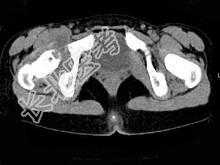

- 单项选择题女,11岁, 肺部有结核病史,二个月前右髋关节有外伤史, 右髋关节部逐渐肿胀疼痛,休息后可减轻, 结合图像,最可能的诊断是 ( )

A、右髋关节结核

B、化脓性关节炎

C、右髋关节退行性变

D、右髋关节类风湿关节炎

E、右髋关节痛风